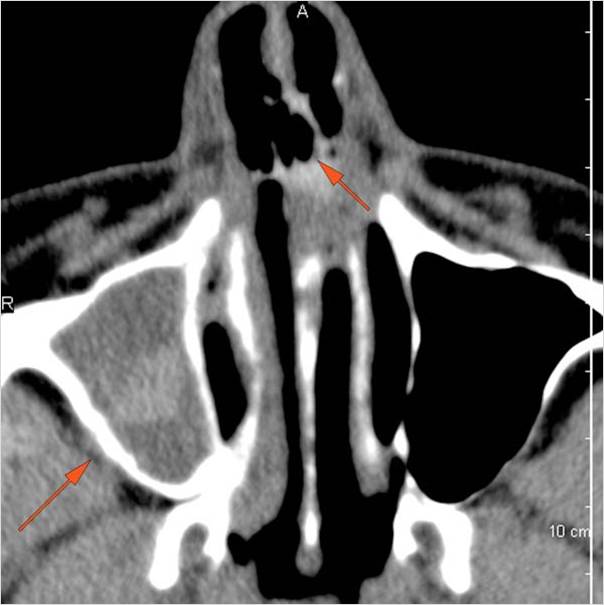

Orbits

The extraconal orbital fat is abnormal. [Yes/No]

There is a subperiosteal abscess or edema along the medial wall, roof or floor of the orbit. [Yes/No]

The extraocular muscles are swollen or otherwise abnormal. [Yes/No]

There is bone erosion along the walls of the orbit. [Yes/No]

The intraconal orbital fat is infiltrated. [Yes/No]

The orbital apex and the superior and inferior orbital fissures are infiltrated. [Yes/No]

The superior and/or inferior ophthalmic veins are dilated or thrombosed. [Yes/No]